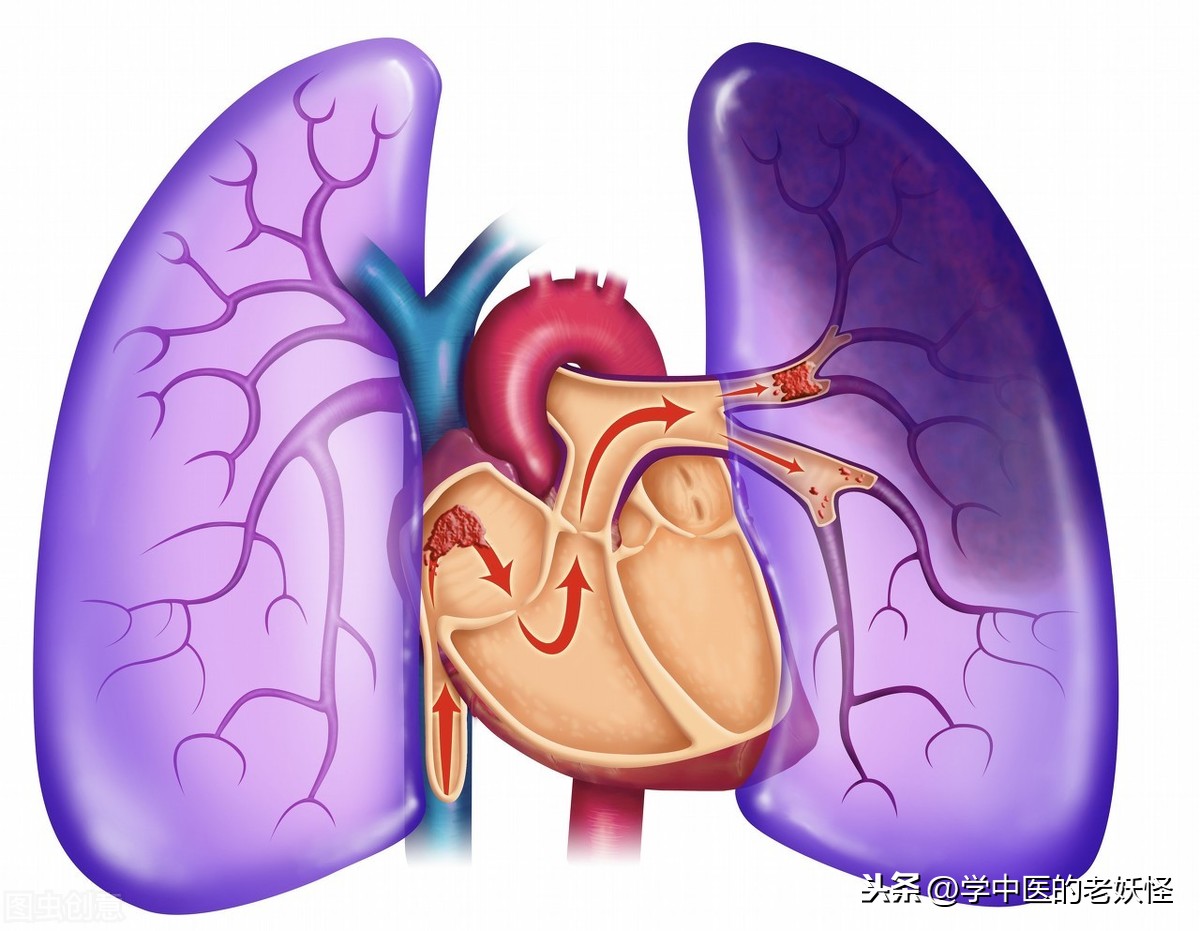

想象一下,我们每天都在呼吸,但你知道吗?这些呼吸的背后,有一群小战士在不停地工作,它们就是肺细胞角蛋白。这些小家伙就像是编织了一张网,紧紧地包裹着我们的肺细胞,保护它们不受伤害。无论是抽烟、空气污染,还是病毒的侵袭,它们都首当其冲,用它们那坚韧的身体,为我们挡下一次又一次的攻击。

有时候,我会想,如果没有这些肺细胞角蛋白,我们的肺会变成什么样?可能就像是一座没有守卫的城池,随时都可能被敌人攻破。所以,每当我深吸一口气,我都会在心里默默地感谢这些小英雄,感谢它们无时无刻不在保护着我们。